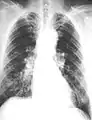

The abnormal chest x-ray and its interpretation remain the most important factors in establishing the presence of pulmonary fibrosis.[11] The findings usually appear as small, irregular parenchymal opacities, primarily in the lung bases. Using the ILO Classification system, "s", "t", and/or "u" opacities predominate. CT or high-resolution CT (HRCT) are more sensitive than plain radiography at detecting pulmonary fibrosis (as well as any underlying pleural changes). More than 50% of people affected with asbestosis develop plaques in the parietal pleura, the space between the chest wall and lungs. Once apparent, the radiographic findings in asbestosis may slowly progress or remain static, even in the absence of further asbestos exposure.[25] Rapid progression suggests an alternative diagnosis.

Extensive fibrosis of pleura and lung parenchyma.

Severe pleural fibrosis with focal calcification.

61 yr old working industrially with asbestos for decades.